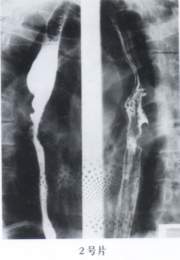

2.(2号片)

A、食管良性狭窄

B、食管憩室

C、喷门失弛缓症

D、中段食管癌

E、食管平滑肌瘤

答案:1—6:EDACAC 15—20:ACBDED